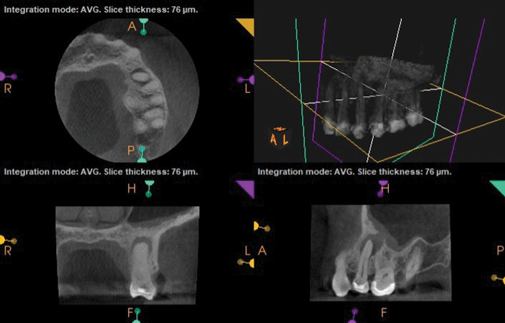

Fig 7 and Fig 8. Preoperative CBCT scans showing evidence of periapical pathology on tooth No. 14 as well as communication with the adjacent maxillary sinus and associated mucositis. Fig 7: Sagittal view, buccal roots No. 14. Fig 8: Sagittal view, palatal root No. 14.

Fig 8. Preoperative CBCT scans showing evidence of periapical pathology on tooth No. 14 as well as communication with the adjacent maxillary sinus and associated mucositis. Fig 7: Sagittal view, buccal roots No. 14. Fig 8: Sagittal view, palatal root No. 14.

Fig 10. CBCT imaging at 3-month follow-up showing signs of healing and decrease in maxillary sinus mucositis. Fig 10: Sagittal view, buccal roots No. 14. Fig 11: Sagittal view, palatal root No. 14.

Fig 11. CBCT imaging at 3-month follow-up showing signs of healing and decrease in maxillary sinus mucositis. Fig 10: Sagittal view, buccal roots No. 14. Fig 11: Sagittal view, palatal root No. 14.